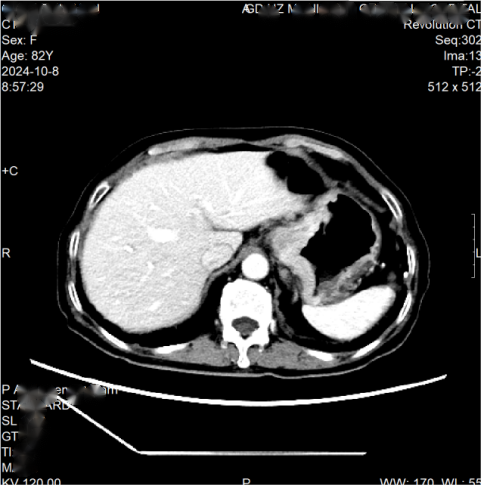

2024年10月9日行全腹平扫+增强+重建提示:贲门部、胃底胃壁不均匀增厚,注意恶性肿瘤可能,贲门周围、网膜囊及腹膜后多发肿大淋巴结(图2)。